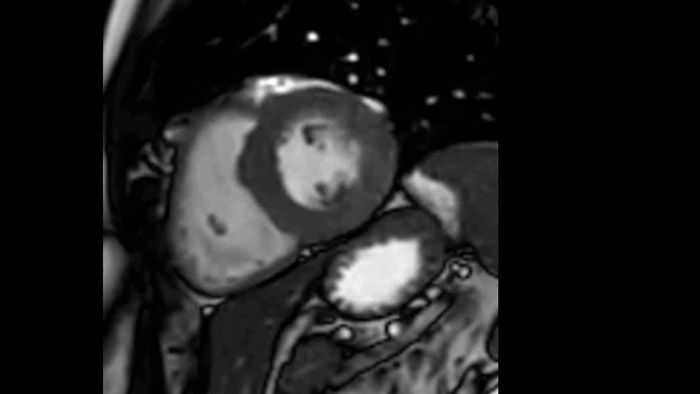

La diagnostica tradizionale non offre la visibilità necessaria per vedere gli effetti di un trattamento cardiaco o individuare disfunzioni prima che si verifichino i sintomi. Combinando la sequenza di acquisizione MRI Fast-SENC di Philips con lo strumento di analisi MyoStrain di Myocardial Solutions, i lievi cambiamenti precoci nella funzione cardiaca possono essere misurati direttamente.

La diagnostica odierna spesso non è in grado di rilevare le disfunzioni cardiache fino a quando non si manifestano sintomi. MyoStrain valuta la deformazione del miocardio in 48 segmenti cardiaci e fornisce ai medici uno strumento diagnostico utile per identificare con anticipo la disfunzione funzionale prima che il cuore nel suo complesso sia compromesso.